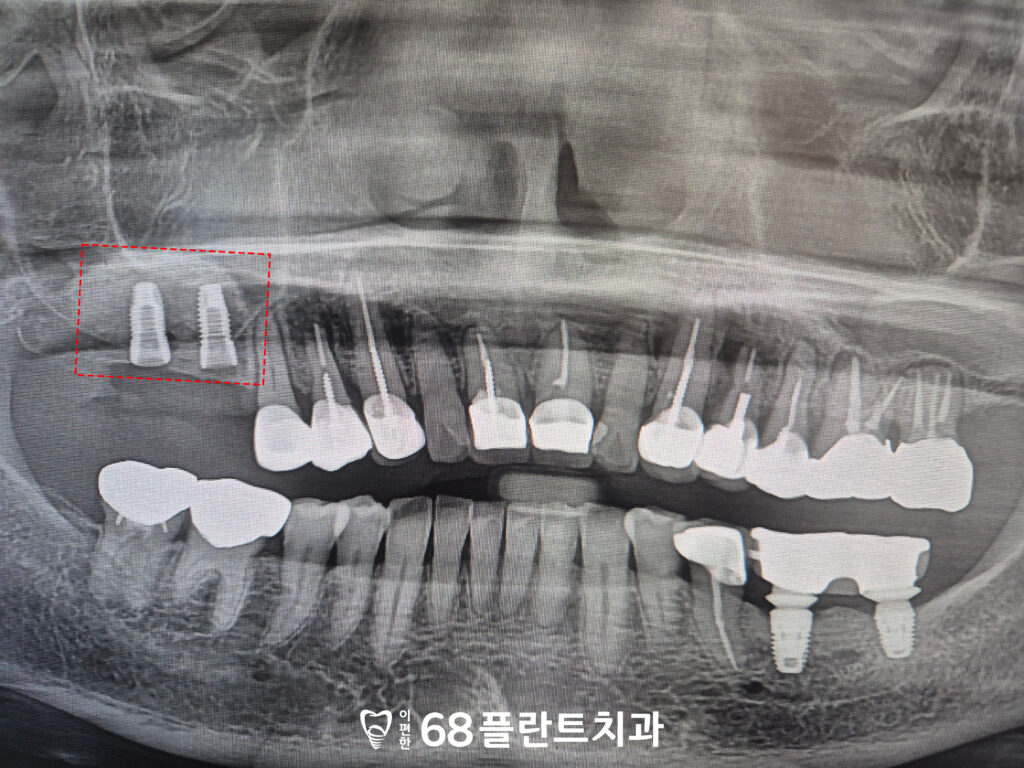

이후 이식한 뼈와 임플란트의

치유기간을 기다렸습니다.

상악동거상술이 동반되었기 때문에

주의사항을 더욱 자세히 설명드렸으며,

특히 치유 과정 동안 과도한 압박이나

충격을 피하는 것이

중요하다고 말씀드렸습니다.

또한, 정기적인 치과 방문을 통해

임플란트와 뼈의 결합 상태를

확인할 수 있도록 하였습니다.